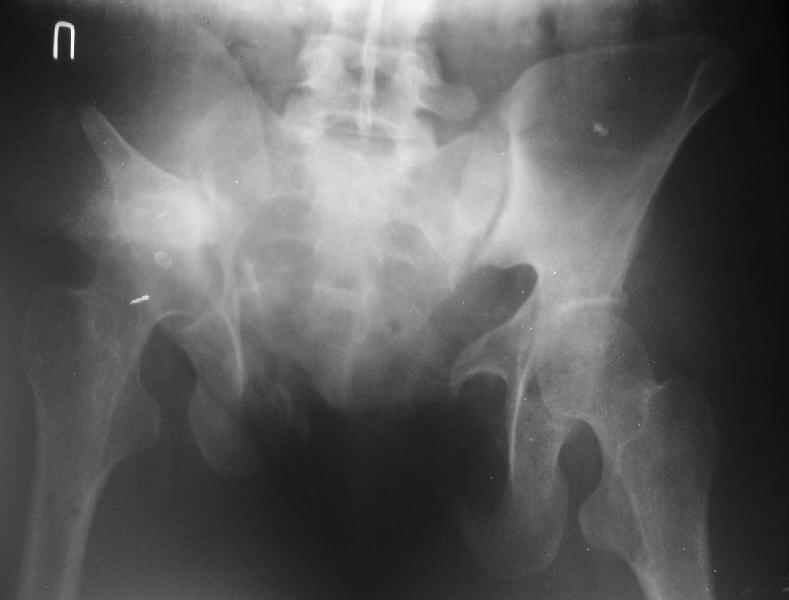

Картина на сегодня:

В настоящее время больная ходит без дополнительной опоры, боль в области таза не беспокоит, неудобств при сидении не испытывает, свободно проходит расстояние в 2-3км. Отмечается незначительная хромота, периодические боли в поясничной области низкой интенсивности, не требующие приема медикаментов, кроме того имеется вагинальный импинджемент. Срок после операции 1 год и 2 месяца.Было бы интересно услышать ваши комментарии. С уважением Агалаков М.В.